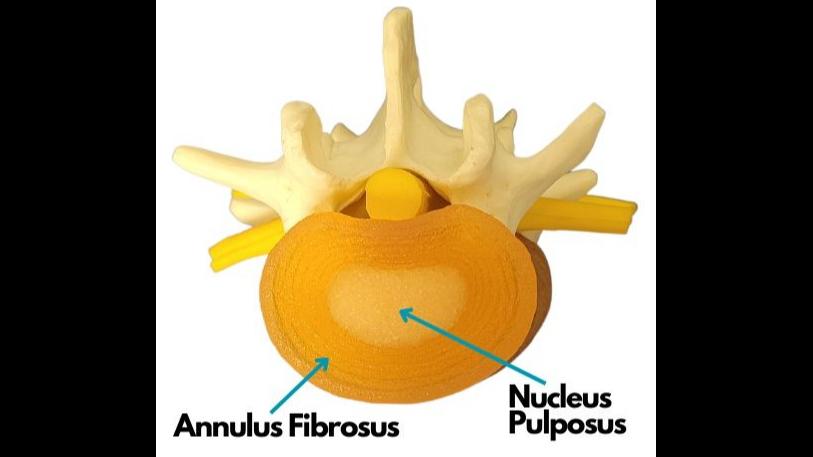

Thereporthastwokeyaims,writtenmostlyto berelevanttoanyonesufferingwithabulging disc,herniateddisc,ruptureddisc,or degenerativediscdisease,thoughitwillalso proveveryusefulandinformativetomany others,andanyonedealingwiththetopicof spinaldiscconditionsitself,